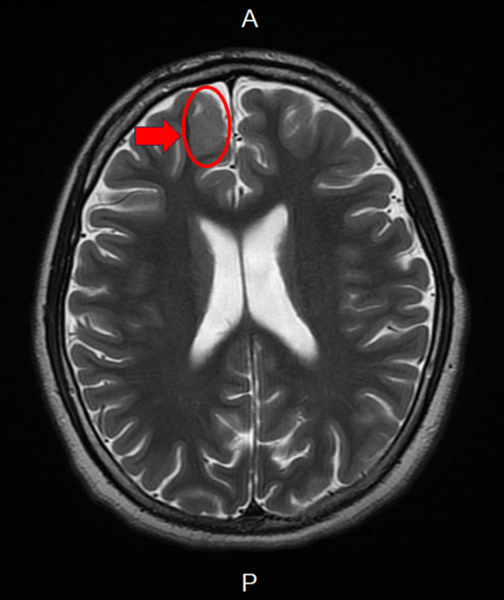

▲張寶玲醫師診察發現男孩有腦皮質發育不良(如箭頭所示)情形。 (圖/記者蔣彤雲攝)

新竹臺大分院小兒部張寶玲醫師評估後發現,男孩腦波檢查出現頻繁右側額葉局部癲癇波,懷疑可能存在腦部病灶,進一步安排腦部磁振造影檢查後,發現右側額葉異常病灶。由於病人屬於頑固性癲癇,在多種抗癲癇藥物治療下仍持續發作,醫療團隊評估後建議接受癲癇手術。

手術過程中透過腦皮質腦波監測,由張寶玲醫師即時判讀並定位癲癇來源,再由神經外科醫師切除病灶,術後病理報告證實為局部腦皮質發育不良,男孩術後恢復良好,未出現併發症,也未再發生意識喪失,癲癇發作次數明顯減少。

張寶玲醫師表示,局部腦皮質發育不良屬於腦皮質發展畸形的一種,也是兒童癲癇手術最常見的病理原因,雖然這類病變並非惡性腫瘤,但若引發癲癇,仍需積極評估是否需要外科手術治療。